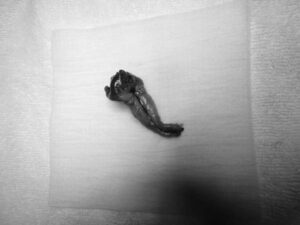

ワンちゃんが乳腺にできた複数のシコリを気にされて来院されました。bilateral mastectomyで対応しました。摘出後の病理組織検査の結果は、「R3-4間腫瘤:乳腺癌(複合型)」でそれ以外は「良性乳腺混合腫瘍」でした。無事元気に退院し、その後再発もなく経過は良好です。よかったね。